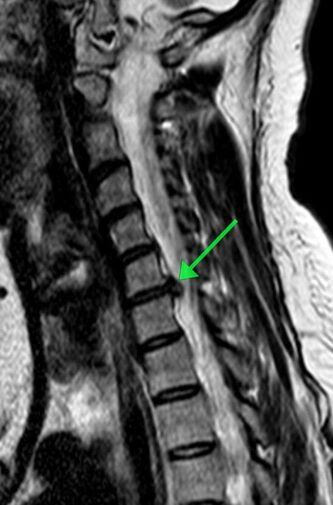

Пациентка обратилась с жлобами на изматывающую боль в руке. Ей провели МРТ, которое показало, что в шейном отделе сформировалась грыжа размером 8 мм. По словам медиков, образование сдавливало спинномозговой канал и корешковое отверстие, угрожая двигательной функции.

«Мы провели сложнейшее микрохирургическое вмешательство, в ходе которого удалили грыжу и стабилизировали позвоночник с помощью современного импланта», — рассказал нейрохирург Николай Карпов, отметив, что операция длилась два часа 20 минут.